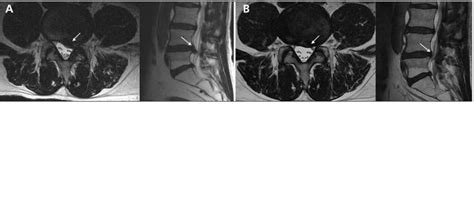

Stuburo išvarža MRT nuotraukoje

Stuburo išvaržos - dažna stuburo patologija, kylanti dėl degeneracinių tarpaslankstelinių diskų pokyčių. Jų metu pažeidžiamas disko geltonosios ir skaidulinės žiedų vientisumas bei išstumiamas kremzlinis branduolys. Išvaržų dažnis didėja su amžiumi ir yra siejamas su stuburo apkrovos veiksniais.

Dažniausiai išsivysto juosmeninės arba kaklinės stuburo dalies išvaržos. Jos gali spausti nervinius audinius bei sukelti radikulopatiją - skausmą, parestezijas ir silpnumą galūnėse. Esant juosmens išvaržai, atsiranda radikulopatinis skausmas, spinduliuojantis palei pažeisto nervo šaknelę. Taip pat gali atsirasti jutimų, motorikos ir refleksų sutrikimų pažeisto nervo inervuojamoje srityje. Jei išvarža kaklinėje dalyje, skausmas ar maudimas gali būti jaučiamas rankoje, o iš juosmens - migruoti į sėdmenis ar kojas.